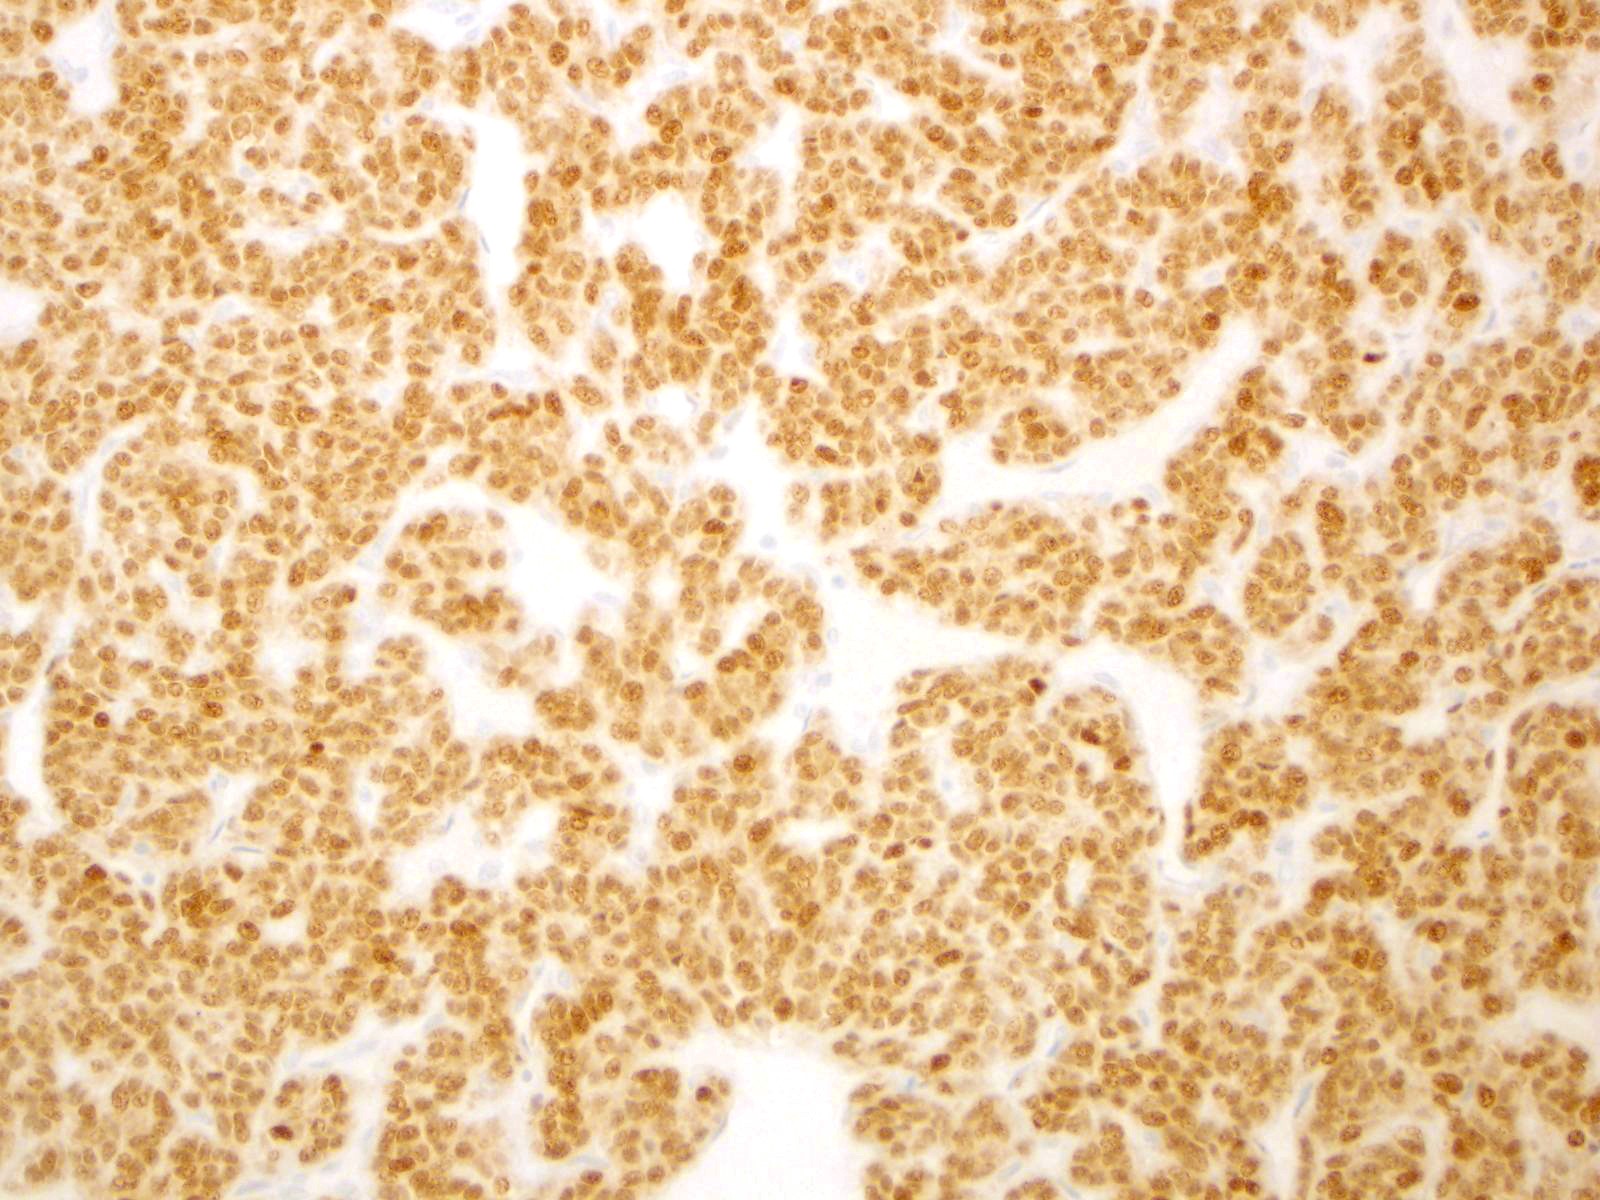

| 2SC |

S-(2-succino)-cysteine |

Rabbit polyclonal (Cambridge Research Biochemicals)

Hereditary leiomyomatosis and renal cell carcinoma (HLRCC) syndrome-associated RCC and leiomyoma

Most renal tumors and leiomyomas not associated with HLRCC

Staining Pattern

Cytoplasmic and nuclear

| HLRCC-associated RCC |

| Non-HLRCC-associated RCC |

| HLRCC-associated leiomyoma |